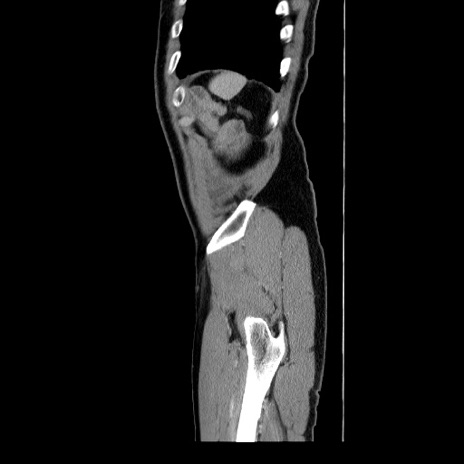

症例34(矢状断像)

【症例】60歳代 男性

【主訴】右鼠径部膨隆

【現病歴】1年程前より右鼠径部膨隆あり。自己にて還納可能だったため放置していた。3時間前より右鼠径部の脱出を認め、還納困難となり受診。

【既往歴】高血圧

【身体所見】右鼠径部に小児頭大の膨隆あり。弾性硬であり、用手還納は困難。左鼠径部にも膨隆を認める。脱出はなし。